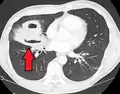

Études d'imagerie

Les abcès pulmonaires sont souvent d'un seul côté et concernent les segments postérieurs des lobes supérieurs et les segments apicaux des lobes inférieurs, car ces zones dépendent de la gravité en position couchée. La présence de niveaux air-fluide implique une rupture dans l'arbre bronchique ou, rarement, la croissance d'un organisme gazogène.[réf. nécessaire]

Un abcès sous-pleural.